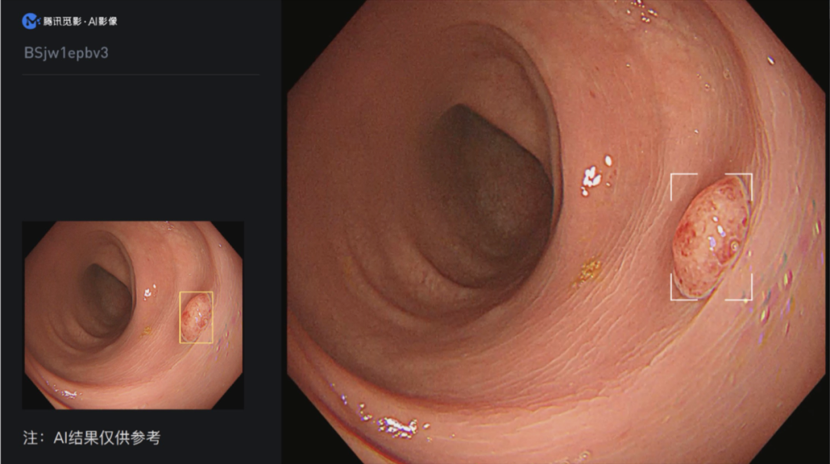

“结肠息肉电子内窥镜图像辅助检测软件”需配合结肠镜检查,从电子内窥镜图像处理器输出的视频流中导入视频图像信号,经过深度学习算法分析后将疑似息肉位置在视频中进行实时标记,提醒医生关注疑似病灶。

在浙江省人民医院、温州市中心医院采用临床试验路径进行的临床评价表明,和常规结直肠镜检查相比,“结肠息肉电子内窥镜图像辅助检测软件”辅助下的结直肠镜检查能有效提升息肉检出率。